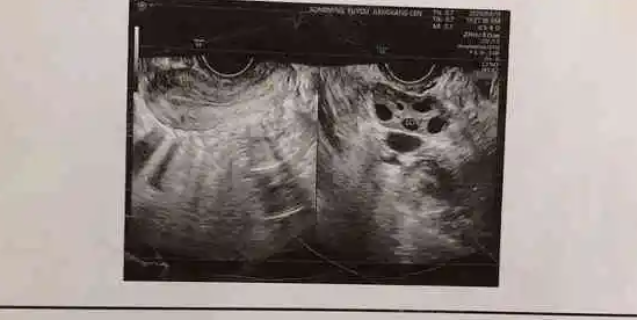

子宫多囊,又称多囊卵巢综合征(PCOS),是一种与女性生殖系统有关的内分泌失调疾病。这种病症在妇女中非常常见,主要特点是卵巢增大、囊肿形成、雄性激素水平过高。